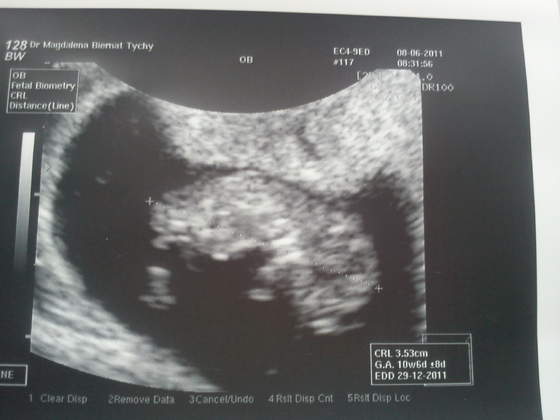

Ja mam nadzieje, ze juz dzisiaj zmieni sie to jak postrzegam moja ciaze, bo wreszcie zobacze po poludniu mojego Bobo